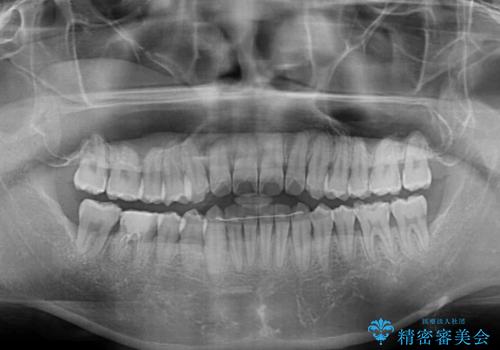

今回は、ワイヤー装置を併用することなく治療を行い、トラブルなく、満足のいく歯列に整えることができました。

矯正治療の途中でホームホワイトニングを併用され、術前とは見違えるほどきれいな口元となりました。